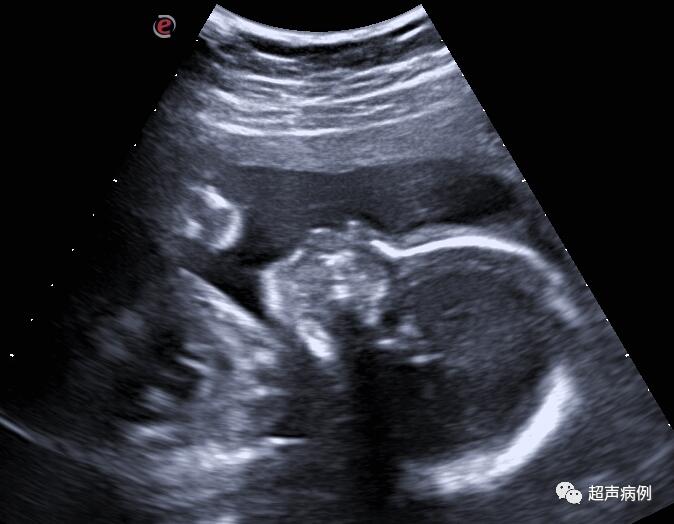

妇科医生也毫不知情,开的妇科超声检查,超声探头刚放上,“哦,怀孕了啊,停经多少周了?”

张珊差点从床上跳起来,瞪大眼睛问:“不可能吧?我还以为长肿瘤了。那大概多久怀上的?能流产吗?流产后还能再生孩子吗?”